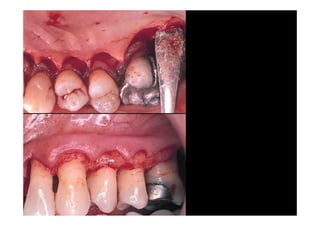

SEPARION OF

INTERDENTAL

PAPILLAE

Modified papailla

preservation technique

BUCCAL DISPLACEMENT

OF INTERDENTAL

PAPIALLAE

POSTOPERATIVE

VIEW